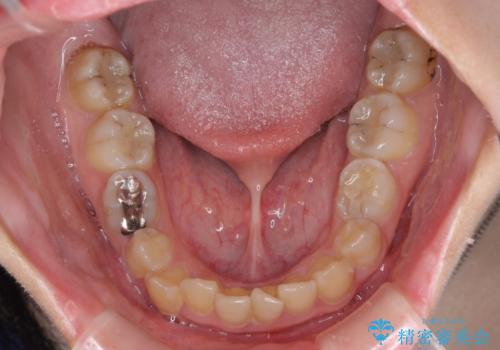

- 犬歯のクロスバイトを気にして来院された患者様です。

マウスピース矯正とワイヤー矯正の両方を提案しましたが、インビザラインの自己管理が煩わしいとのことで、ワイヤー装置による矯正治療を行うこととしました。

犬歯は歯根が太くて長いため、クロスバイトを改善するのは大変であることが多いですが、比較的スムーズに改善することができました。